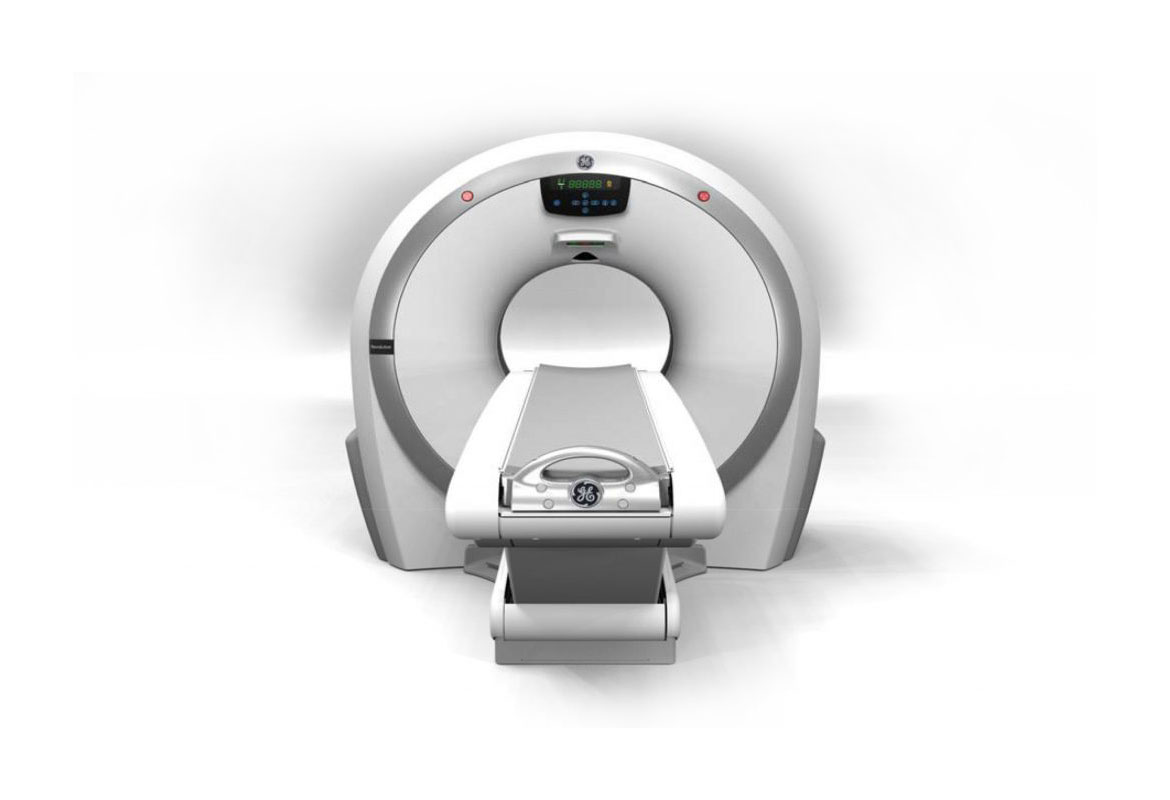

Компьютерный томограф Revolution ACT от GE Healthcare точный и производительный. С его помощью врачи и пациенты получают надежные данные для более точных диагнозов и оптимального планирования лечения.

Аппарат оснащен передовыми технологиями, которые обеспечивают высокое качество изображений с низкой дозой радиации. Он предлагает четкие и детализированные изображения анатомических структур и позволяет врачам получать информацию о внутренних органах и тканях пациента с высокой разрешающей способностью.

Технические характеристики:

- Диаметр тоннеля 65 см

- Мощность генератора 24 кВт

Количество срезов 16/32

Одним из ключевых преимуществ Revolution ACT является его способность снижать дозу радиации, не ухудшая качество изображений. Это осуществляется благодаря инновационной технологии ASiR-V (Adaptive Statistical Iterative Reconstruction-Vevo), которая реконструирует итоговое изображение, используя данные из предыдущих итераций. Так лучевая нагрузка уменьшается до 40%, а время сканирования сокращается.

Улучшенная визуализация

Revolution ACT наследовал прорывную разработку GE — сегментированную, фокально-ориентированную конструкцию детектора Clarity. Благодаря ей достигается снижение шума до 20% и улучшается качество изображения. Алгоритм IQ Enhance ускоряет время сканирования до трех раз и позволяет пациентам задерживать дыхание на более короткие промежутки времени.

Удобный рабочий процесс

Эргономичный дизайн консоли Revolution ACT создавался с учетом предпочтений рентгенологов и лаборантов.

На ней оператор делает на 79% меньше кликов, чтобы провести сканирование. Аппарат запускается быстрее, а данные о пациенте подтягиваются автоматически. Настройки позволяют запускать исследование после достижения заданной плотности контрастного вещества и демонстрировать изображения в реальном времени во время исследования.

Низкие эксплуатационные расходы

Выбор в пользу Revolution ACT позволяет исключить или значительно снизить расходы на подготовку помещения к инсталляции и эксплуатационные расходы. Минимальная площадь для аппарата – 10,1 кв. м. Система вполовину легче аппаратов предыдущего поколения и обладает меньшим энергопотреблением. Каждый детекторный канал аппарата потребляет всего 2 мВт. В детекторе реализовано интеллектуальное управление температурным режимом, поэтому подготовка к сканированию занимает несколько минут. Рост эффективности помогает существенно снизить операционные расходы учреждения.